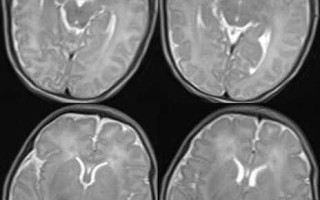

新生儿健康护理 新生儿胆红素脑病早期临床表现 第一阶段:警告期(通常出现于出生后2-7天)这个阶段的症状可能比较轻微且不典型,但已经预示着病情正在进展,家长和医护人员需要高度警惕,嗜睡与反应差: 这是最常见的早期信号,宝宝不像平时那样清醒,总是想... 99ANYc3cd6 2025-11-27 0 #新生儿胆红素脑病早期症状 #新生儿胆红素脑病早期识别 #新生儿胆红素脑病早期表现